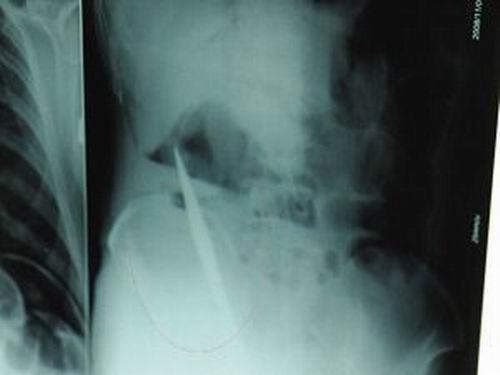

X光片上,尖刀清晰可見。

從男子體內(nèi)取出的尖刀足足有19厘米長。

江蘇銅山一58歲男子因服毒被送到醫(yī)院搶救,可醫(yī)生采取搶救措施后卻發(fā)現(xiàn)效果不佳。后來經(jīng)細(xì)致檢查,醫(yī)生有了個(gè)驚人的發(fā)現(xiàn),該男子的體內(nèi)竟然有一把尖刀,醫(yī)生通過手術(shù)將位于其腹部右側(cè)橫結(jié)腸下緣的尖刀取了出來。這把尖刀足足有19厘米長!據(jù)醫(yī)生推測,這把刀應(yīng)該是從肛門推進(jìn)體內(nèi)的,不知男子為何想以如此殘酷的方式結(jié)束自己生命。由于搶救及時(shí),該男子已暫時(shí)脫離危險(xiǎn)。

昨天(11月6日)上午,記者在徐州礦務(wù)集團(tuán)總醫(yī)院重癥監(jiān)護(hù)室見到了這名男子,目前他雖然已經(jīng)恢復(fù)了意識,但還不能開口說話,需要呼吸機(jī)輔助呼吸。據(jù)醫(yī)生介紹,4日中午12時(shí)左右,這名男子因服毒輕生被緊急送到醫(yī)院進(jìn)行搶救,之前,這名男子已經(jīng)在當(dāng)?shù)剜l(xiāng)鎮(zhèn)醫(yī)院進(jìn)行了近20小時(shí)的治療,但效果不佳!安∪吮晦D(zhuǎn)院到礦總院時(shí)已神志不清,血壓極低,處于休克狀態(tài)!本茸o(hù)人員給男子洗胃、初步處理以后,發(fā)現(xiàn)男子呼吸急促,于是趕緊給他拍片檢查。結(jié)果讓所有的醫(yī)生大吃一驚,竟有一把尖狀異物橫在該男子腹腔內(nèi)!當(dāng)天下午5時(shí)30分,輕生男子被推上了手術(shù)臺。經(jīng)過40多分鐘的手術(shù),該男子腹腔被打開,手術(shù)醫(yī)生發(fā)現(xiàn),男子體內(nèi)的金屬狀異物竟然是一把長19厘米的尖刀!

醫(yī)生告訴記者,手術(shù)后,醫(yī)生在病人身上并未發(fā)現(xiàn)刀痕,最后,經(jīng)過檢查發(fā)現(xiàn),在該男子直腸處找到穿孔。醫(yī)生從醫(yī)學(xué)角度分析后認(rèn)為,這把尖刀應(yīng)該是從肛門插入直腸的。